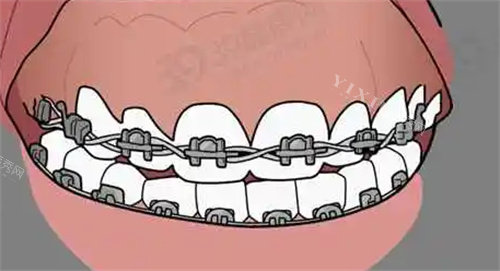

一、金属托槽矫正

金属托槽矫正是比较经典、技术比较成熟且经济实惠的矫正方式。

国产金属托槽矫正:价格大约在 6500元至12000元 之间,适合预算有限、对美观性要求不高的患者。

进口金属托槽矫正:价格相对较高,约 8000元至20000元,其材料和工艺更为可靠。

二、自锁托槽矫正

自锁托槽矫正技术在传统金属托槽基础上进行了改进,减少了摩擦和不适感,矫正速度相对更快。

国产金属自锁矫正:价格区间约为 8000元至15000元。

进口金属自锁矫正:价格较高,约 10000元至25000元,矫正结果更佳。